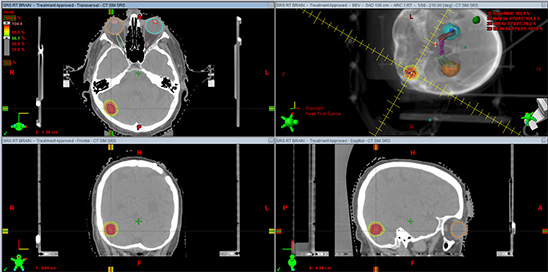

家人辗转求医最终找到INC德国巴特朗菲教授,王女士的治疗才迎来转机。在教授所在的德国INI国际神经学研究所、由INC德国巴特朗菲教授主刀的一场高质量手术直接全部切除了患者大脑深部复杂部位的脑膜瘤,她大脑中的“定时炸弹”被彻底摘除。如今手术已过去了1年半,从其术前MR、刚手术后的MR、术后1年半多的MR可以清楚看到未见复发迹象,患者现在一切生活如常,幸福的晚年生活不必再被可怕的肿瘤打扰。

术前MR

术后一年半MR